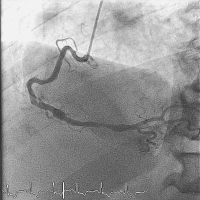

Abbildung 3: Angiographische Darstellung des teilthrombosierten RCA-Aneurysmas mit disloziertem Stent (Pfeil).

Keywords:

Aneurysma

,

Angiographie